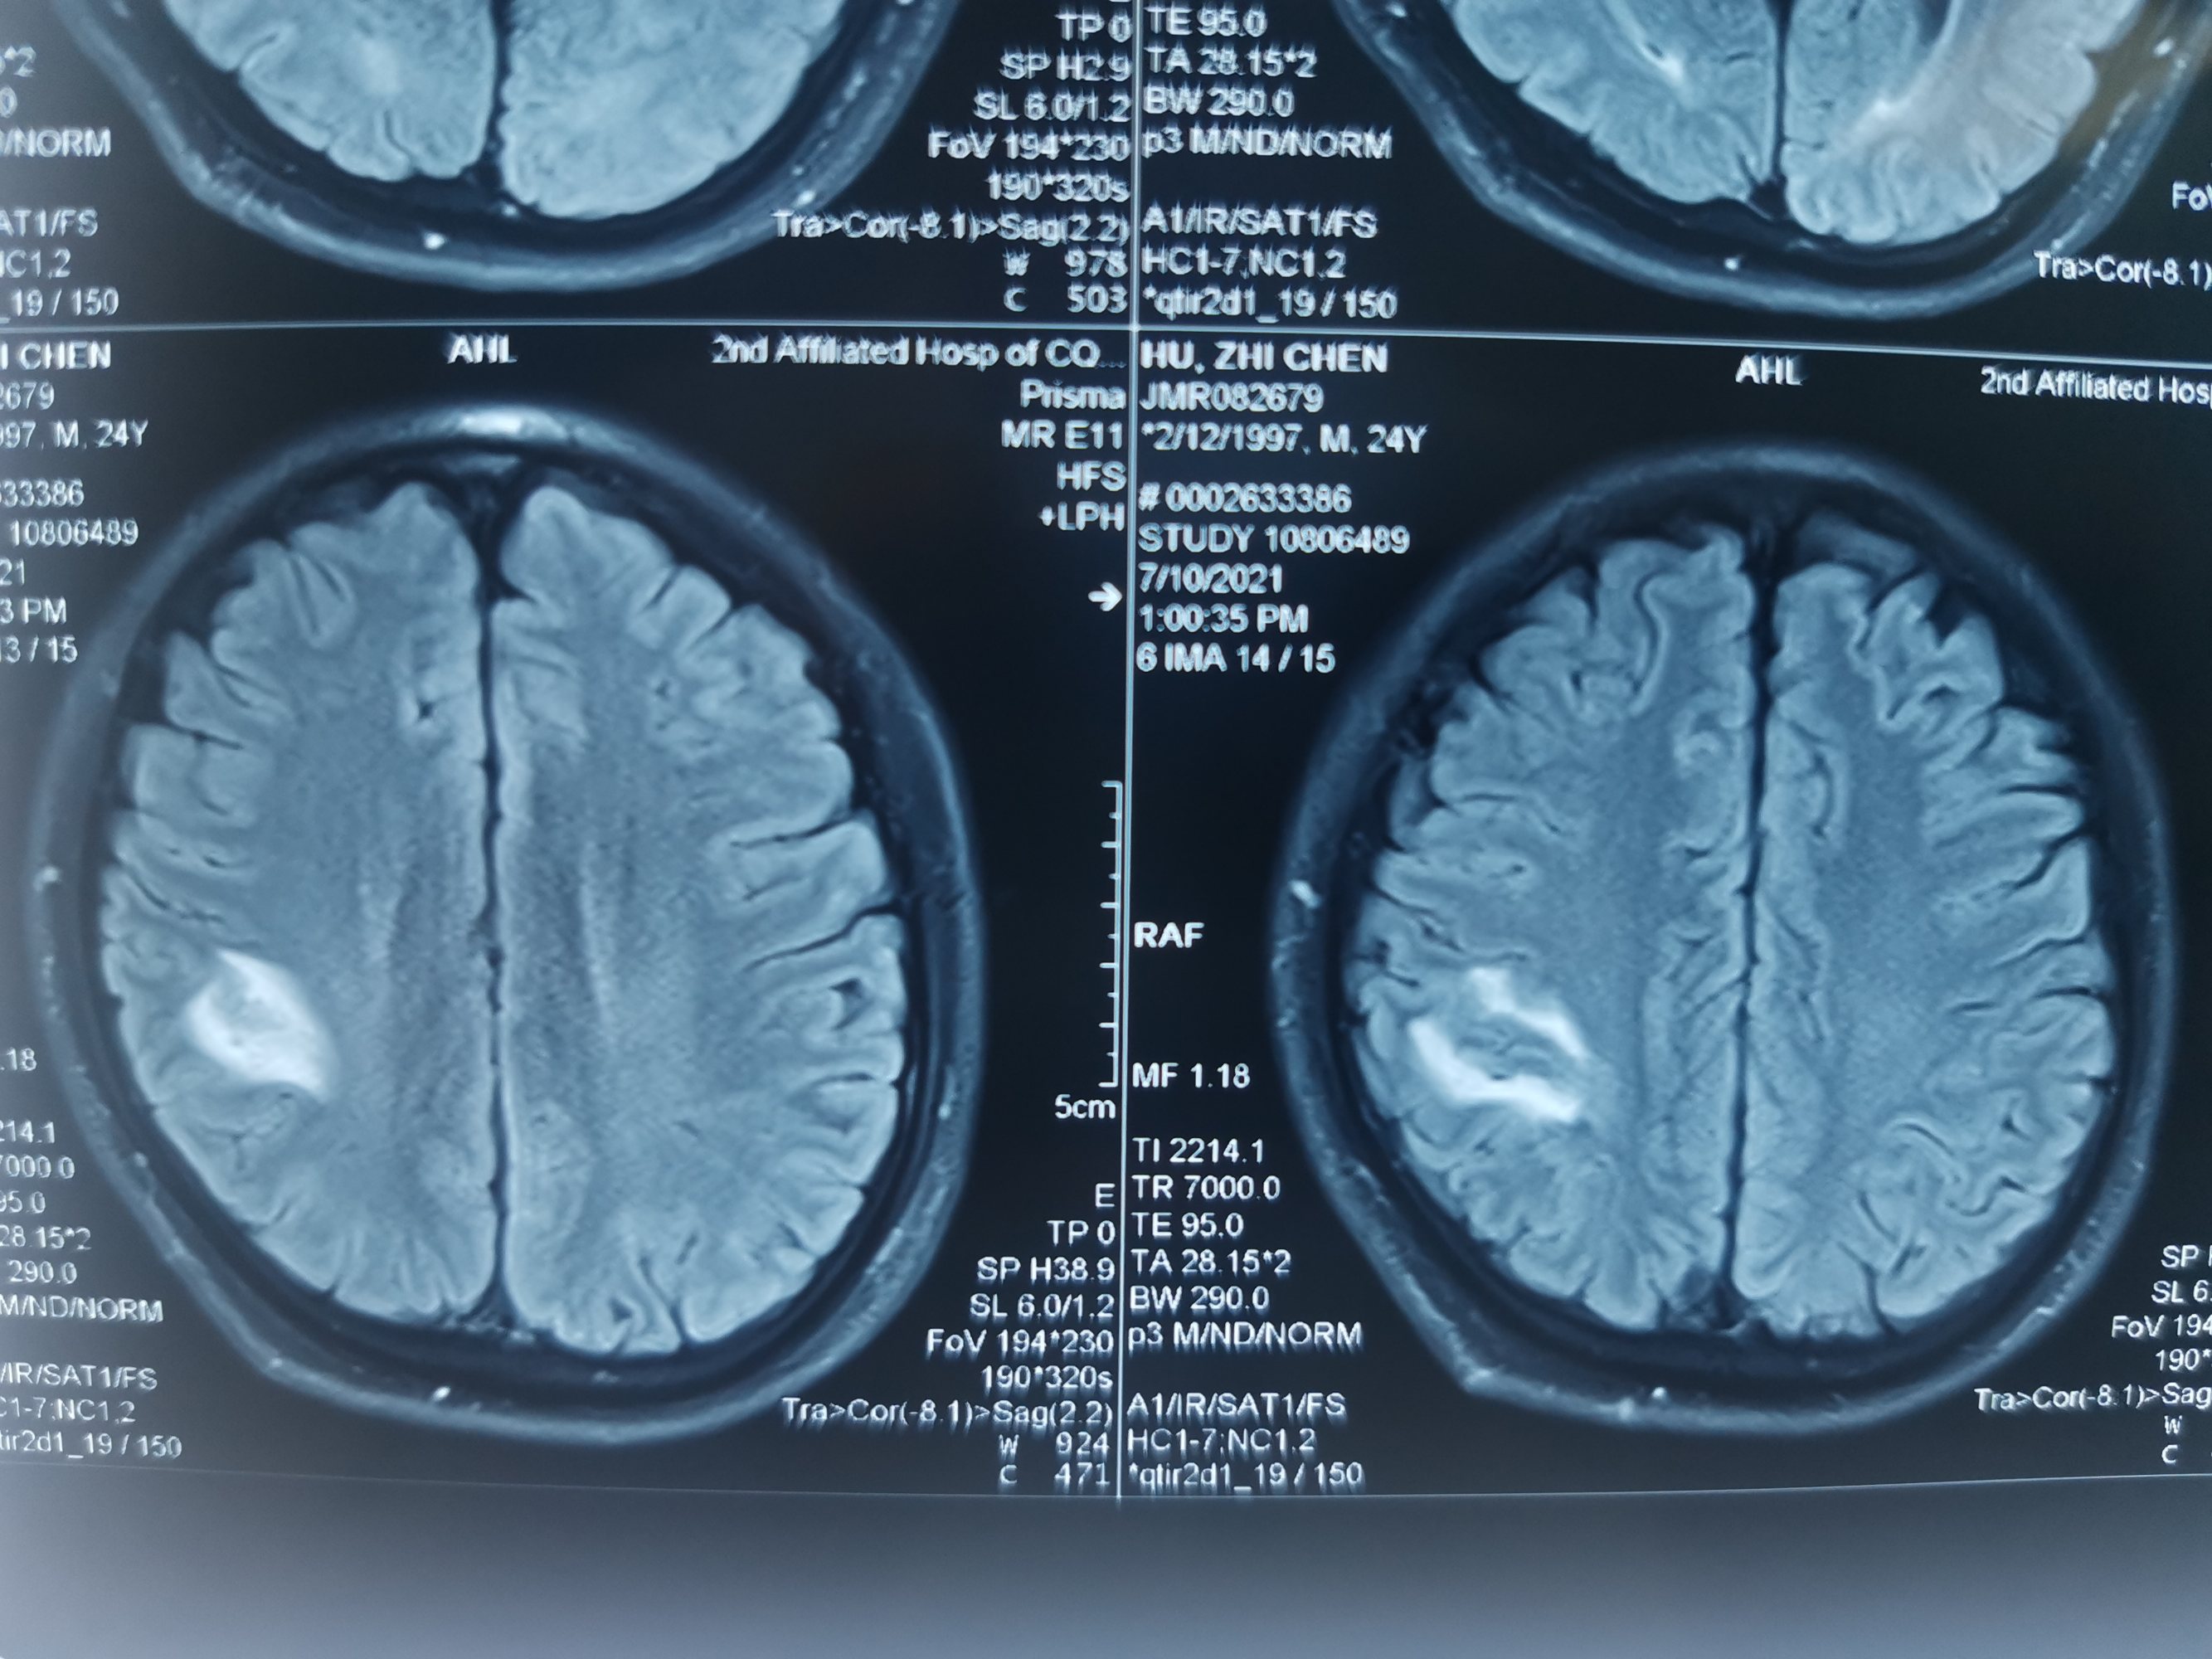

外院磁共振提示右侧顶叶病变

入院后急查头颅磁共振发现顶叶又新发两个病灶。

磁共振发现顶叶又新发两个病灶

DWI考虑新发病灶为脑梗死,考虑该梗塞病灶位于运动皮层导致患者右下肢完全偏瘫。

磁敏感成像考虑首发病灶为出血。